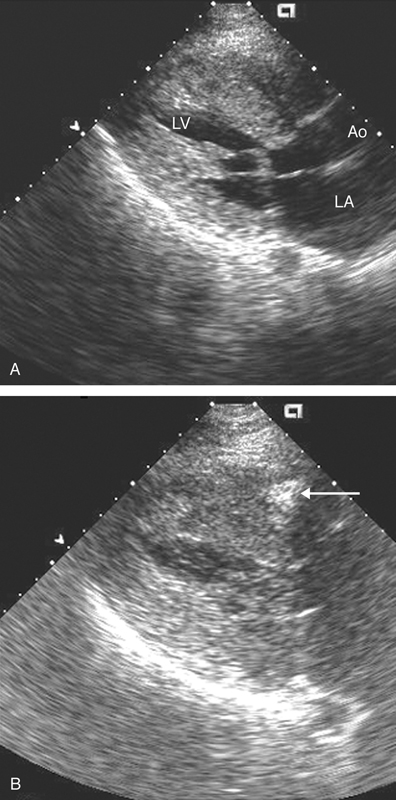

فحوصات تشخيصية لبعض امراض القلب والشرايين التاجية